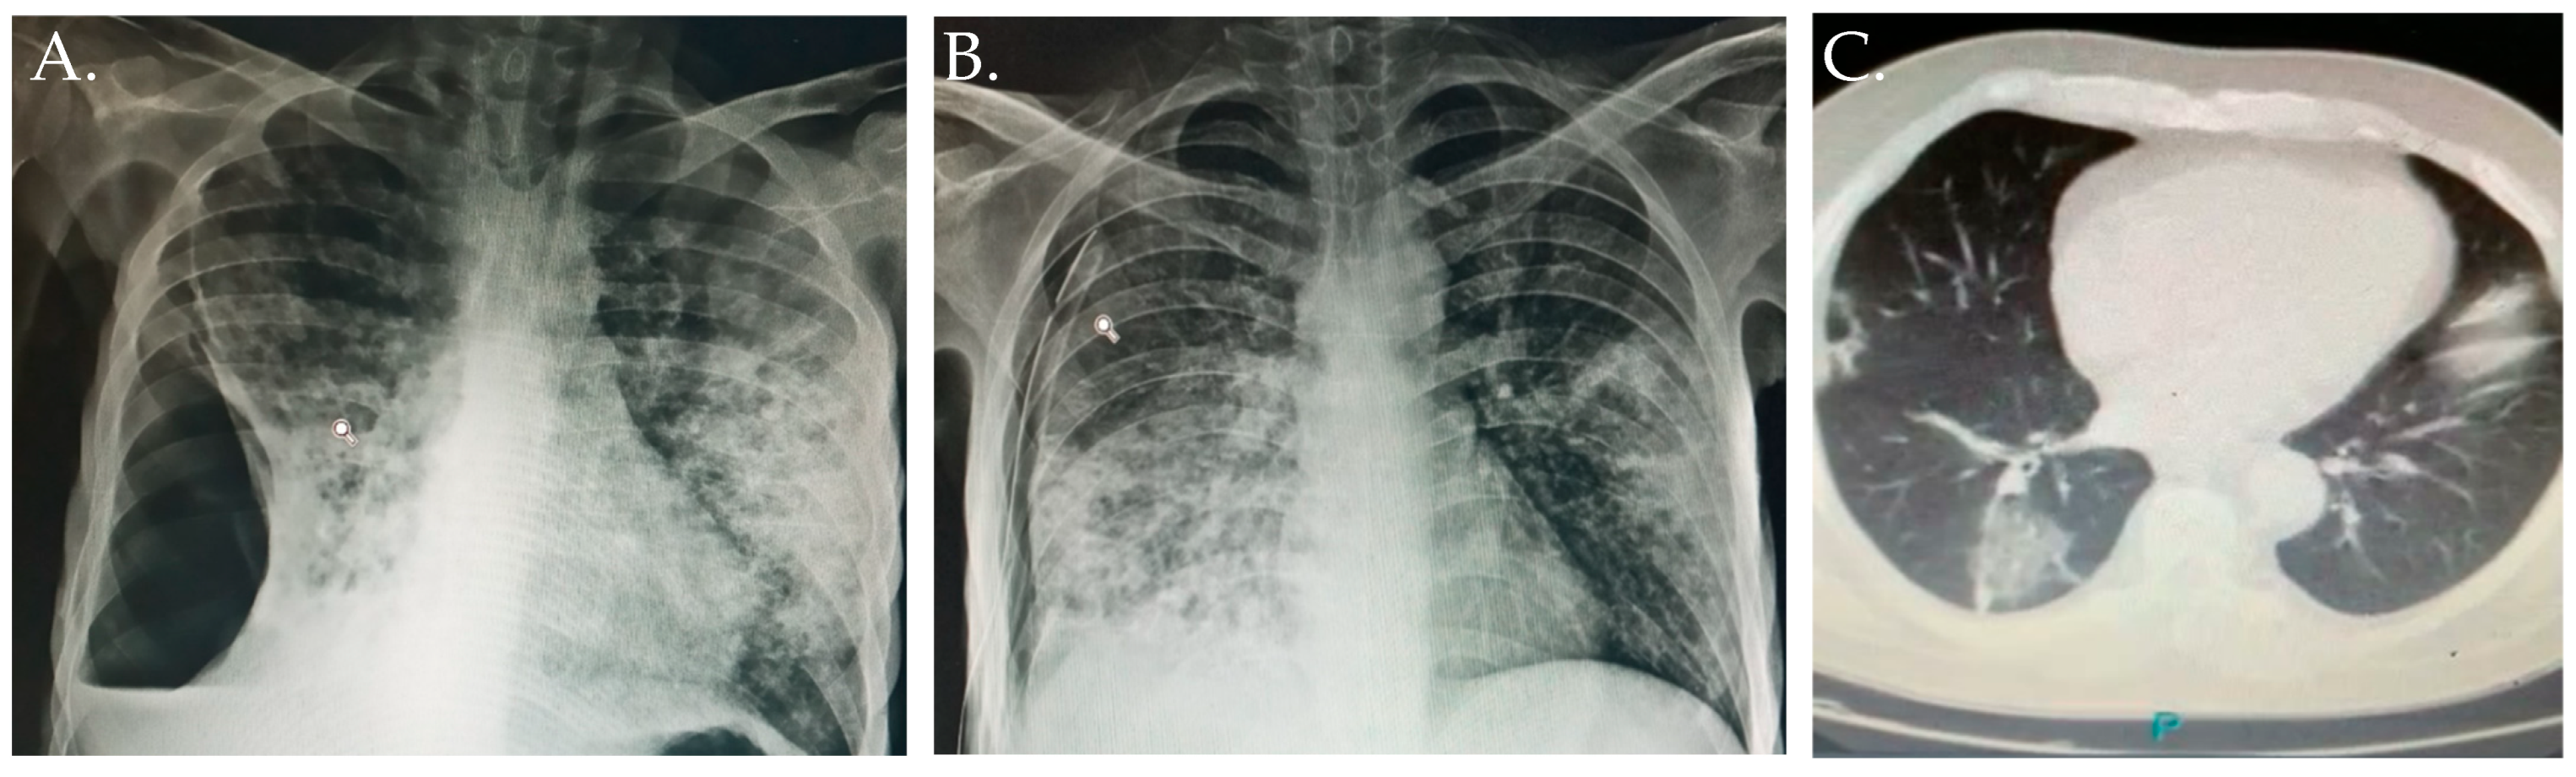

3.1. Case Report 1

3.2. Case Report 2

3.3. Case Report 3